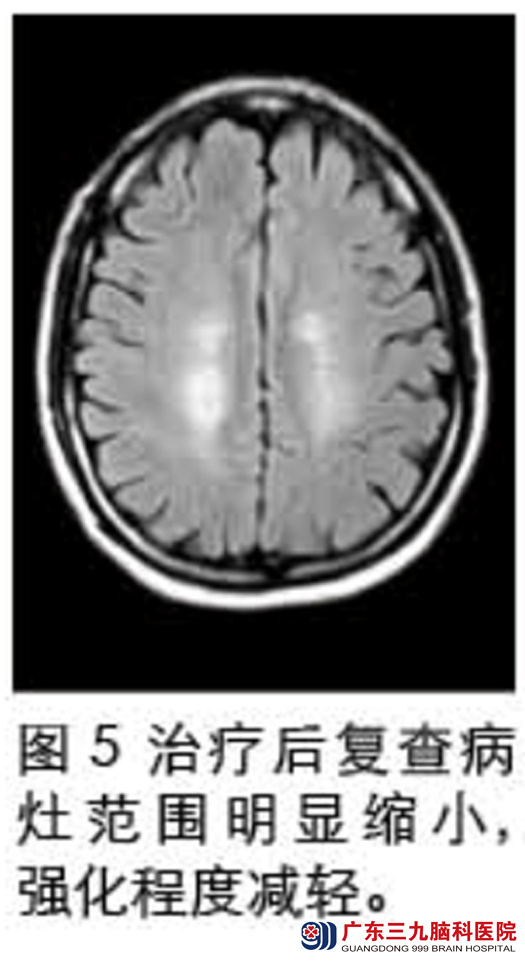

入院查体见双下肢肌力减退,肌张力偏高,腱反射亢进。头部磁共振检查示:双侧半卵圆中心多个长T1长T2病灶(见图1),伴强化(见图2),DWI序列ADC值升高(图3),MRS提示Cho峰稍有升高,NAA峰有所下降,Cr峰未见明显变化,可见Lip/Lac峰(见图4);腰穿结果:脑脊液常规正常,生化提示蛋白升高,寡克隆带阳性。确诊为Balo同心圆硬化,给予激素冲击、营养神经治疗。治疗后复查头部磁共振提示:颅内多发病灶范围较前明显缩小,异常强化程度较前减轻(见图5)。入院治疗一个月后林先生好转出院。www.999brain.com

以往认为同心圆硬化预后差,近年来国内报道的病例的多数对激素有良好的反应。据林先生的主管医生王玉周称,林先生经过激素冲击后短期内复查磁共振即见影像学明显改善,也说明了这一点。其远期预后尚有待于进一步随访。总之,同心圆硬化起病慢,逐渐进展,对激素治疗反应良好,影像学特征明显,可以通过影像学早期诊断。